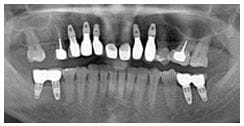

術後X光片